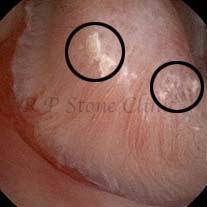

Kidney stone is a solid mass of CRYSTALS. It is the process of crystallization which initiates the formation of kidney stones. This happens in nephrons or units of kidney. Once a small crystal is formed, it can both grow & unite with other crystals leading to the formation of small concretion which eventually forms a stone. Once these large crystals detach from the collecting ducts, the process of stone formation starts in the renal collecting system. A recurrent kidney stone former is advised to know a little bit about something known as Randall’s plaque. Alexander Randall discovered plaques on the renal papillae eight decades back based on examination of 1154 pairs of autopsied Kidneys. He described these renal papillary lesions as cream colored or milk patch areas composed of calcium phosphate & calcium carbonate. These plaques could act as NIDUS for formation of KIDNEY STONE. Calcium Oxalate stone can form on this nidus & then detaches from this plaque to become a free floating stone in the collecting system of kidney

These images are taken as snap shots from the video recording of RIRS Surgery done at our hospital. These are Randall’s Plaques seen with Digital FLEX XC & Digital FLEX XC S. The cream or whitish patches are seen on the tips of RENAL PAPILLAE as seen in images below.

Randall’s Plaques may lead to the formation of Stones.

Those kidney stone patients who have Randall’s Plaques in their kidneys are more likely to form stones again (Recurrent Stones).